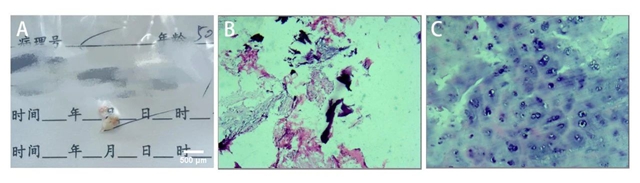

术后病检提示送检组织是退变的髓核组织(A)手术标本 (B-C)病检HE染色